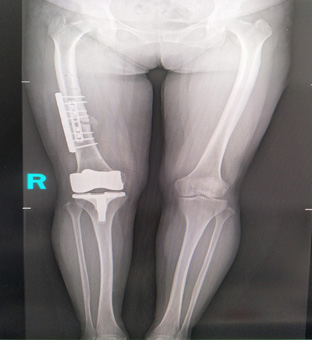

市中醫(yī)醫(yī)院放射科這臺(tái)高端懸吊DR具有千萬級(jí)像素,利用其特有的“無縫拼接”技術(shù),可獲得一幅完整的全脊柱和全下肢影像,為臨床在脊柱側(cè)彎畸形和下肢骨關(guān)節(jié)病變?cè)\斷、治療方案制定及術(shù)后復(fù)查提供精準(zhǔn)的測(cè)量。

1、判斷下肢力線,主要用于膝關(guān)節(jié)內(nèi)外翻畸形的測(cè)量,能比較準(zhǔn)確地反應(yīng)骨結(jié)構(gòu)異常和軟組織不平衡對(duì)膝關(guān)節(jié)內(nèi)外翻的最終影響。對(duì)膝關(guān)節(jié)置換的X線評(píng)估尤為重要。

這一DR全景成像技術(shù)是基于全自動(dòng)拼接技術(shù),能夠有效地滿足臨床應(yīng)用的需要,相對(duì)既往技術(shù)水平來說,這一技術(shù)是一個(gè)很大的突破。